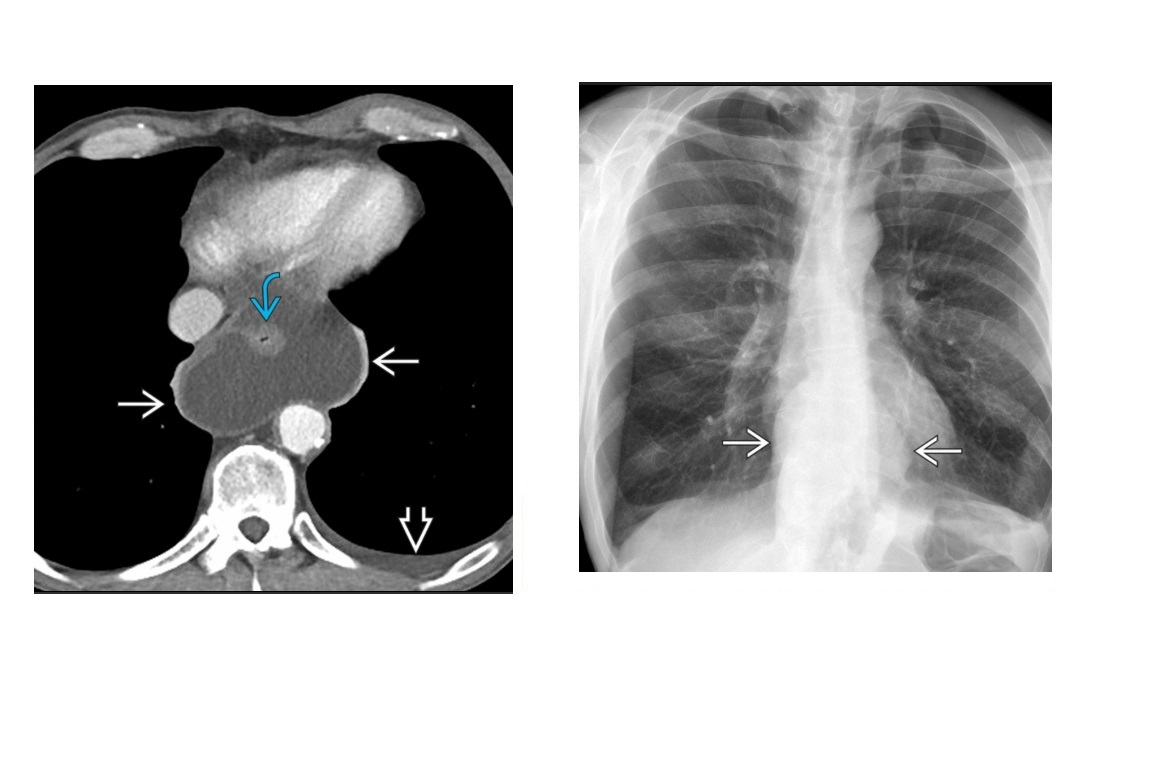

Sigmoid Vovulus Inverted U shape Ahaustra Coffee bean - cleft is double thickenss of opposed bowel loops Directed toward right upper quadrant (RUQ) or left upper quadrant (LUQ); Look for - Gas in proximal small bowel and colon Abscence of air in rectum Tend to be older patients Mx with rectal decompression